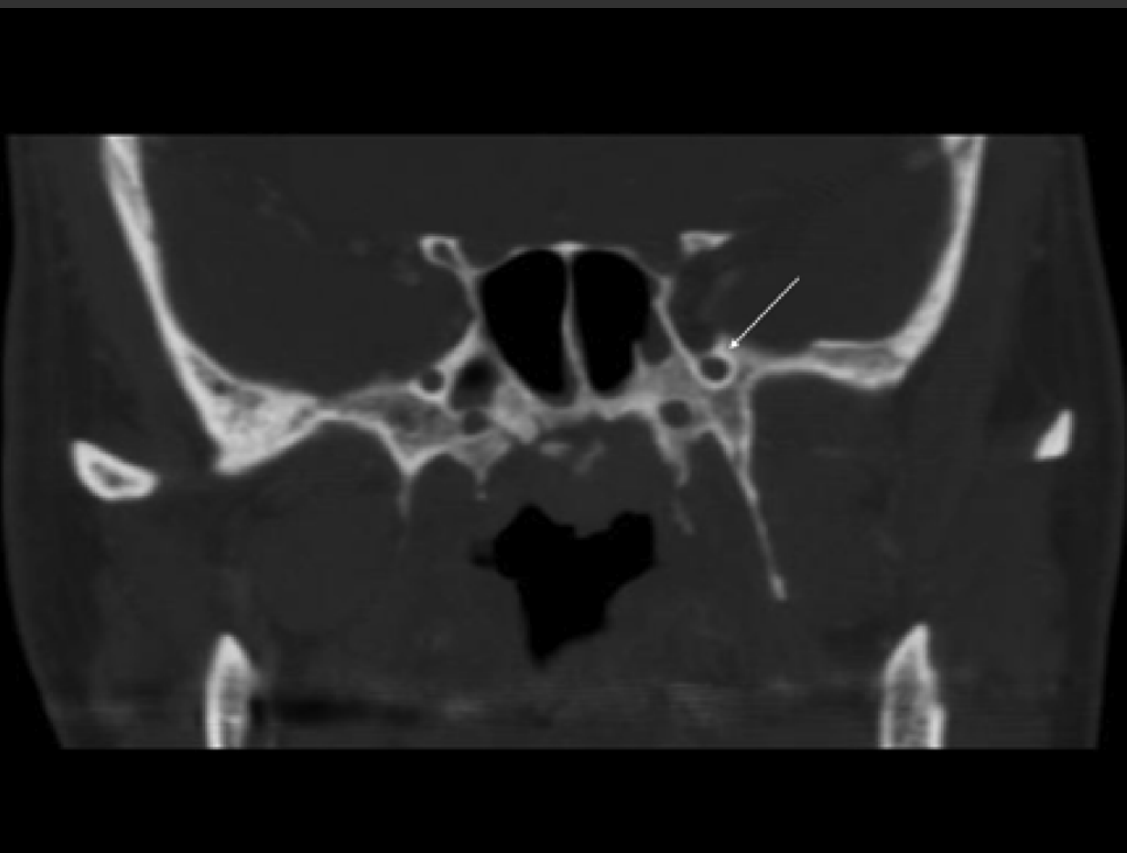

What structure passes through the foramen demonstrated with the white arrow?

A. V2